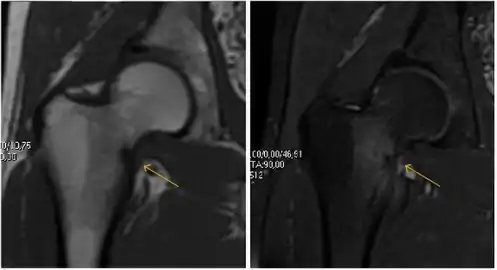

Figure 9:

Sagittal T1 weighted image showing anterosuperior labral tear.[1]

Sagittal T1 weighted image showing anterosuperior labral tear.[1] Sagittal T1 weighted image showing chondral lesion.[1]

Sagittal T1 weighted image showing chondral lesion.[1] Sagittal CT-arthrography showing posteroinferior chondral injury.[1]

Most of the angles and measurements described in the plain radiograph section can be accurately reproduced on MRI. In addition, the superiority of MRI resolution with intra-articular contrast allows detection of labral and chondral abnormalities that may influence the choice of medical, percutaneous, or surgical management (Figure 9).[1]

MR arthrography has proven superior in accuracy when compared to native MR imaging. It is considered the best technique to assess the labrum. Knowledge of the normal variable morphology of the labrum helps to differentiate tears from normal variants. A triangular shape is most commonly seen in 66% of asymptomatic volunteers, but round, flattened, and absent labra can also be found in asymptomatic populations. MR arthrography has demonstrated sensitivity over 90% and specificity close to 100% in detecting labral tears. Loose bodies are demonstrated as filling defects surrounded by the hyperintense gadolinium.[1]

Association between labral tears and chondral damage has been demonstrated. This underscores the interaction between cartilage and labrum damage in the progression of osteoarthritis. Chondral damage to the posteroinferior part of the acetabulum as a contrecoup lesion occurs in approximately one-third of pincer cases secondary to persistent abutment on the anterior part of the joint leading to a slight posteroinferior subluxation. This is considered a bad prognosis sign.[1]